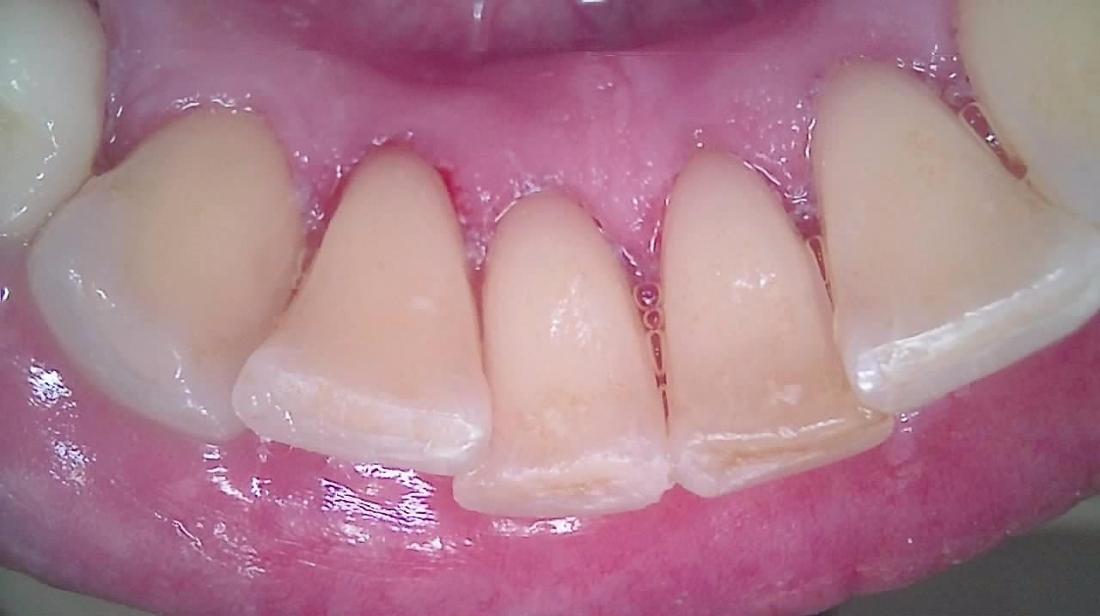

When we clean your teeth, we are removing buildups of calculus.tartar as well as buildups of plaque bacteria on your teeth. Here is a before an after example of a cleaning taken ten minutes apart. After a cleaning, your gum tissues are ready for your home care to help them to become much healthier in the future.